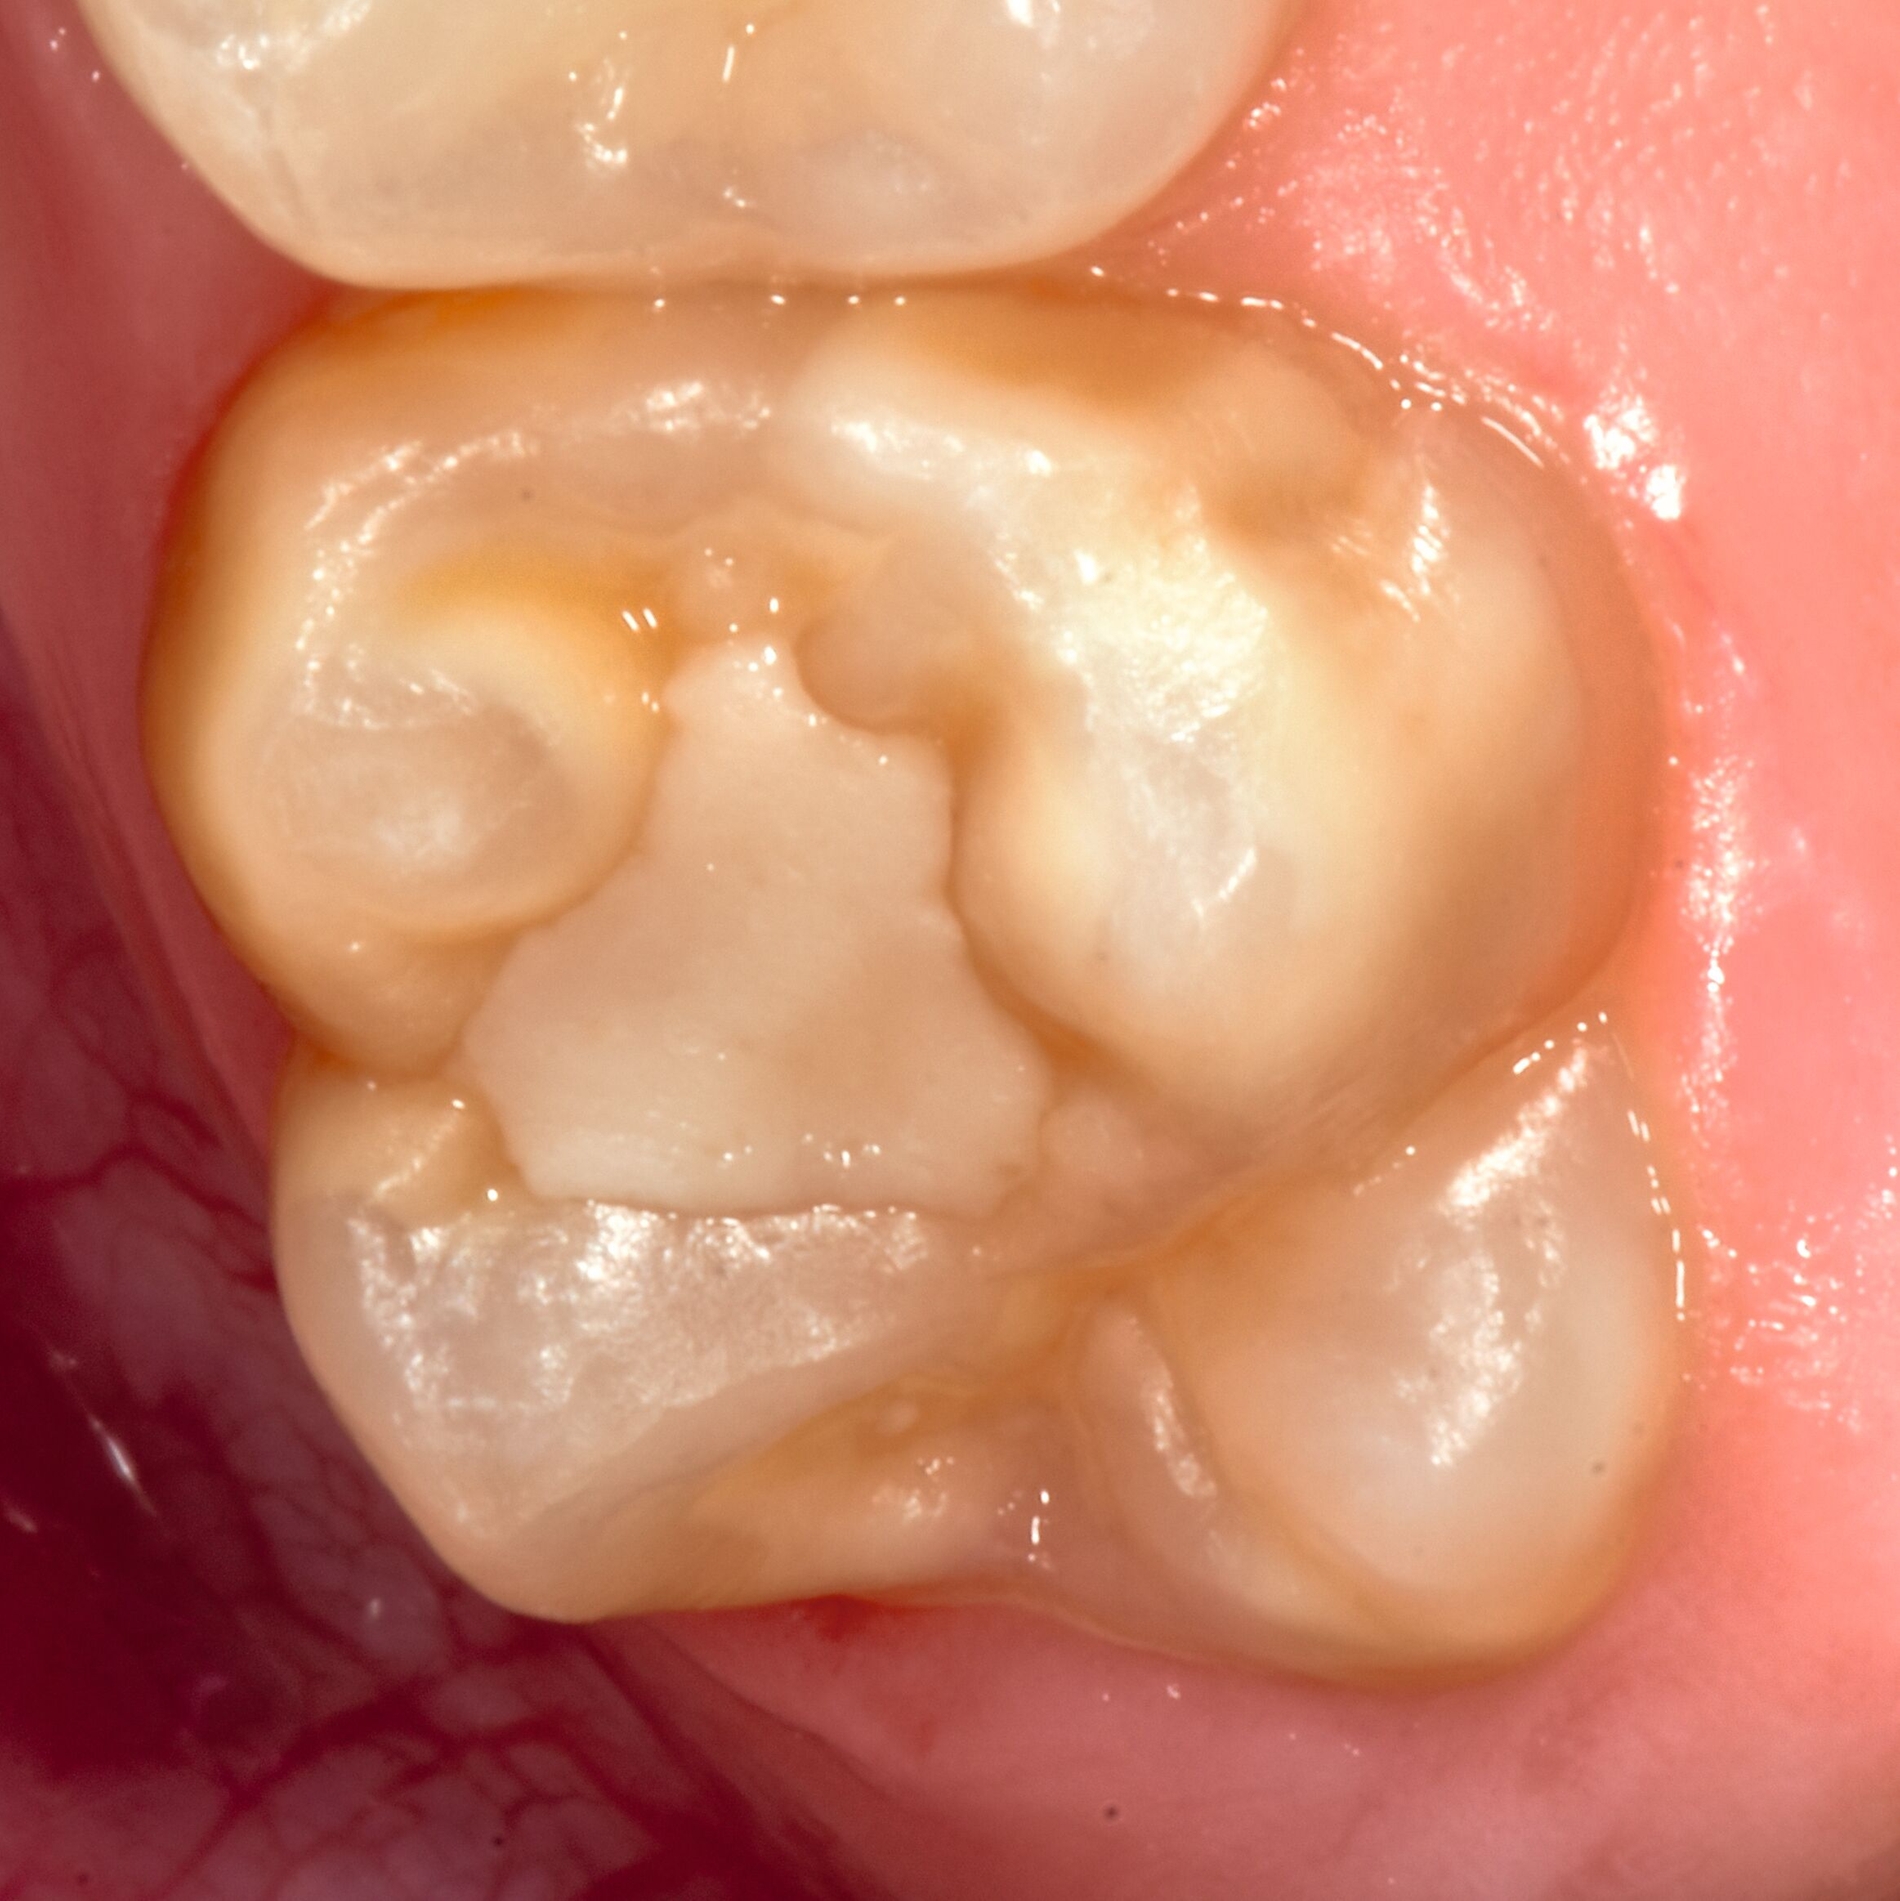

Das klinische Erscheinungsbild an bleibenden Zähnen zeigt typischerweise weißlich-gelbe bis gelblich-braune Opazitäten, die zumindest in einigen Bereichen durch eine scharfe Abgrenzung (engl.:„demarcated opacities“) zum gesunden Zahnschmelz charakterisiert sind (Abbildungen 3 und 4). Die abgegrenzten Hypomineralisationen befinden sich mehrheitlich im Bereich der inzisalen Kronenhälfte unabhängig von dem Auftreten an Front- oder Seitenzähnen. Die Ausprägung am Zahn kann dabei auf einzelne Areale oder Höcker begrenzt sein.

Bei einer schwerwiegenderen Ausprägung sind Zahnflächen vollständig betroffen, mitunter alle Zahnflächen an einem Zahn. Die Verteilung in der Dentition beziehungsweise an den Indexzähnen ist gleichermaßen variabel und betrifft nicht nur die Defektgröße, sondern auch die Farbe und Festigkeit. Was die Festigkeit betrifft, gilt als die Faustregel: Je dunkler die Farbe des Schmelzes, umso weicher beziehungsweise poröser und damit minderwertiger wird dessen Qualität sein. Damit reduziert sich seine kaufunktionelle Belastungsfähigkeit, was insbesondere an ersten bleibenden Molaren von klinischer Relevanz ist.

Für die Dokumentation und Klassifikation der MIH wurden verschiedene Systeme vorgeschlagen. Als historisch und veraltet gilt der (modifizierte) DDE-Index. Demgegenüber haben die Kriterien der EAPD – abgegrenzte Opazitäten (Abbildung 3 und 4), Schmelzeinbrüche (Abbildung 5), atypische Restaurationen (Abbildung 6) – mittlerweile die weiteste Verbreitung gefunden. Diese wurden 2003 erstmals zur Beschreibung der MIH auf empirischer Basis publiziert [Weerheijm et al., 2003] und den Jahren 2010 und 2022 im Rahmen der damaligen MIH-Workshops bestätigt [Lygidakis et al., 2010; 2022].